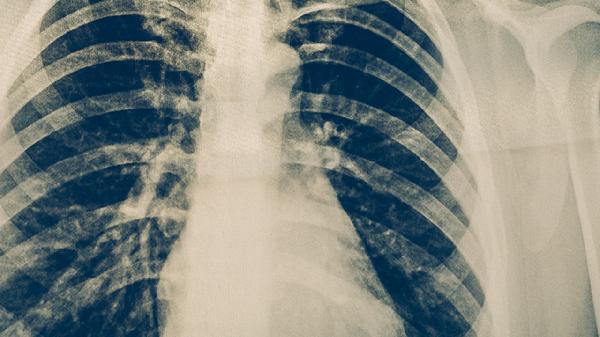

治療期間每月需進(jìn)行痰涂片檢查、胸部X線復(fù)查及肝功能檢測。痰菌轉(zhuǎn)陰后仍需持續(xù)監(jiān)測,防止復(fù)發(fā)。治療2個月末痰菌未轉(zhuǎn)陰者需調(diào)整方案。全程治療通常需6-9個月,耐藥結(jié)核需延長至18-24個月。